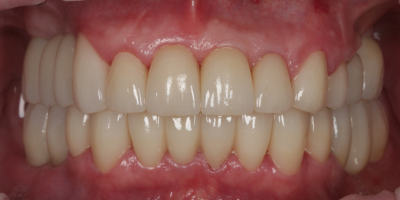

Результат

Комплексное лечение позволило одновременно сохранить собственные зубы и восполнить отсутствующие участки с помощью имплантатов. Временные конструкции обеспечили адаптацию и комфорт сразу после операции. Постоянные циркониевые коронки восстановили гармонию улыбки, прочность и долговечность. В итоге пациент получил полноценный зубной ряд и красивую естественную улыбку.